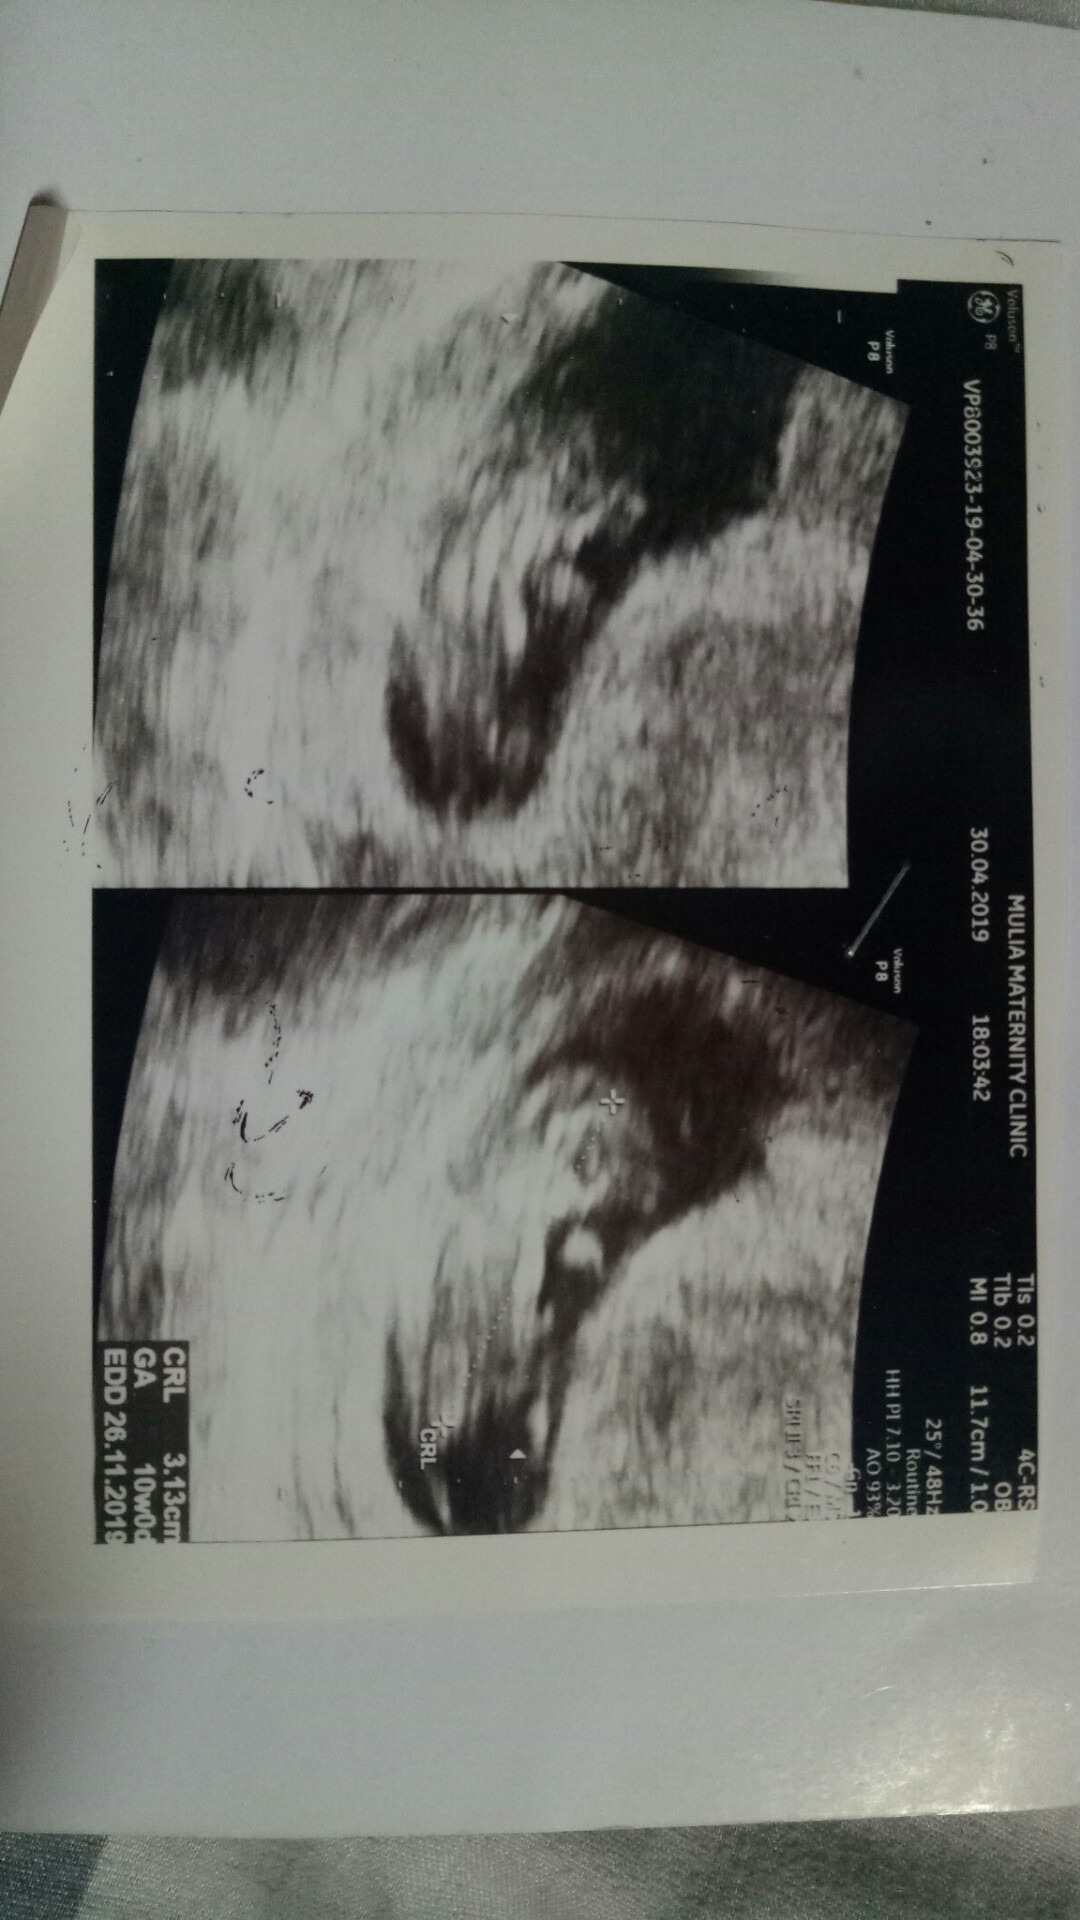

Ini usg sy 10w bun